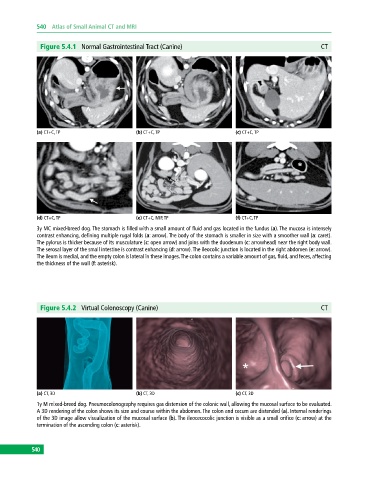

Figure 5.4.1 Normal Gastrointestinal Tract (Canine) CT

(a) CT+C, TP (b) CT+C, TP (c) CT+C, TP

(d) CT+C, TP (e) CT+C, MIP, TP (f) CT+C, TP

3y MC mixed‐breed dog. The stomach is filled with a small amount of fluid and gas located in the fundus (a). The mucosa is intensely

contrast enhancing, defining multiple rugal folds (a: arrow). The body of the stomach is smaller in size with a smoother wall (a: caret).

The pylorus is thicker because of its musculature (c: open arrow) and joins with the duodenum (c: arrowhead) near the right body wall.

The serosal layer of the small intestine is contrast enhancing (d: arrow). The ileocolic junction is located in the right abdomen (e: arrow).

The ileum is medial, and the empty colon is lateral in these images. The colon contains a variable amount of gas, fluid, and feces, affecting

the thickness of the wall (f: asterisk).

Figure 5.4.2 Virtual Colonoscopy (Canine) CT

(a) CT, 3D (b) CT, 3D (c) CT, 3D

1y M mixed‐breed dog. Pneumocolonography requires gas distension of the colonic wall, allowing the mucosal surface to be evaluated.

A 3D rendering of the colon shows its size and course within the abdomen. The colon and cecum are distended (a). Internal renderings

of the 3D image allow visualization of the mucosal surface (b). The ileocecocolic junction is visible as a small orifice (c: arrow) at the

termination of the ascending colon (c: asterisk).